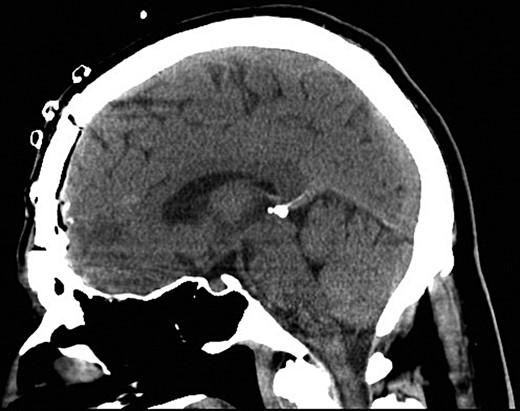

Following the current presentation, he was commenced on levetiracetam and a CT angiogram was performed to rule out an intracranial vascular injury. A preoperative CT slice and three-dimensional (3D) reconstruction of the needles in-situ is provided in Figs 1 and 2.

Preoperative sagittal CT demonstrating six needles traversing through the frontal lobe.